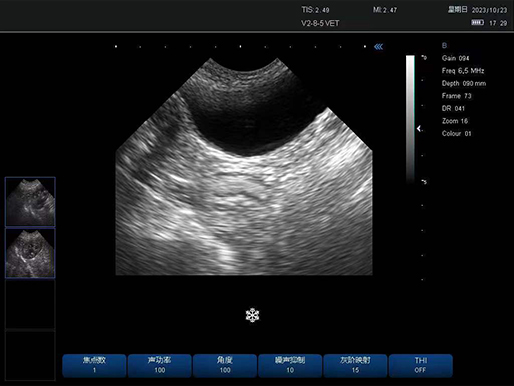

犬 膀胱

犬 膀胱

有关病变的更多见解

凸阵探头-犬 膀胱